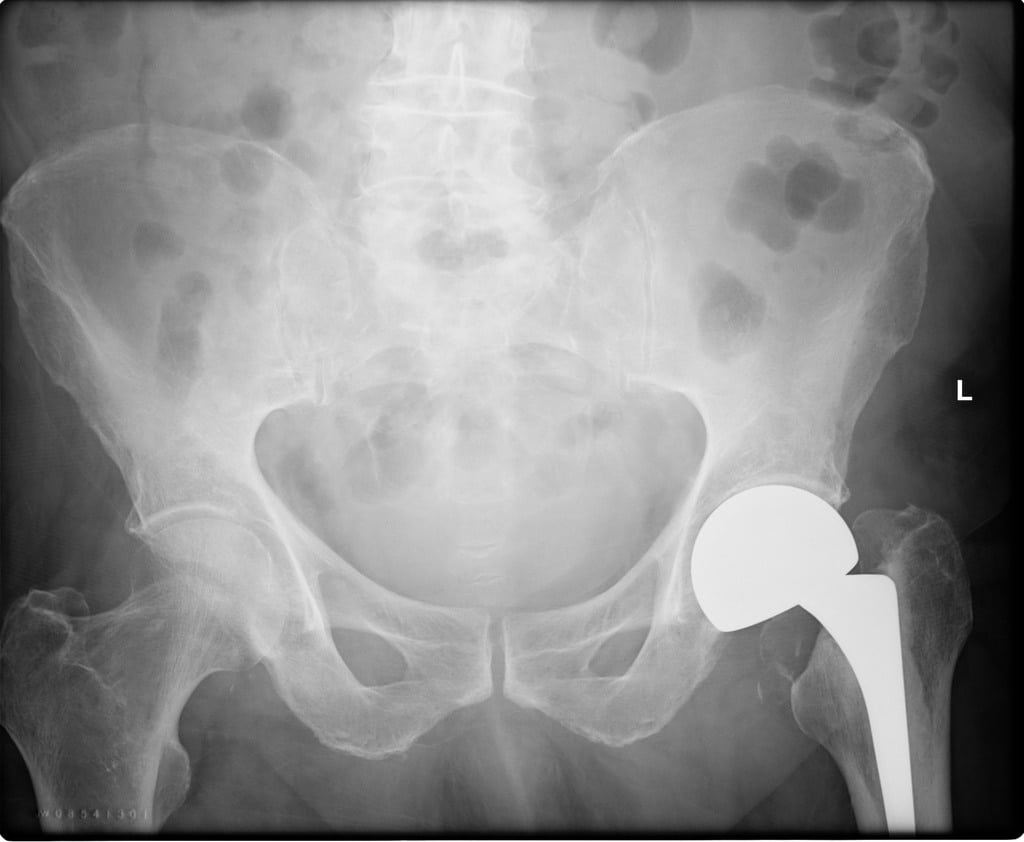

film X ray hip radiograph showing broken bone (fracture femur ) treated by hip replacement Hip Replacement Vs Broken Hip Also called total hip arthroplasty, hip replacement. Hip replacement options are good choices if the fracture damages the blood supply to the ball part of your hip joint. Hip revision surgery repairs or replaces a hip replacement, as well as fractures around your prosthesis. You may need revision surgery due to wear and tear or difficulties with your. Hip fracture. Hip Replacement Vs Broken Hip.